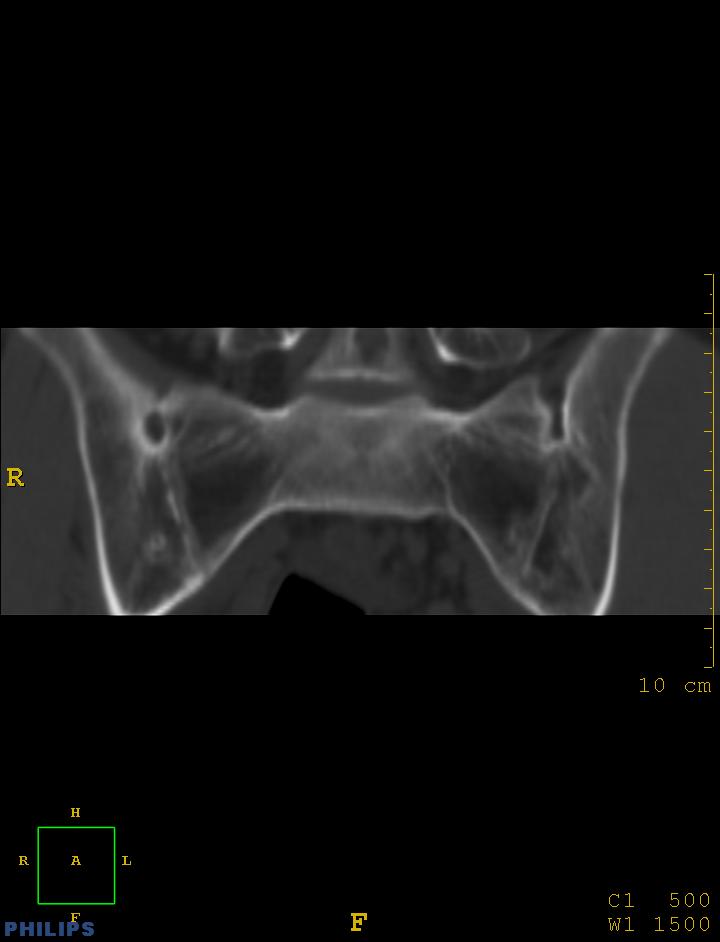

m,34岁,腰痛三年,腰椎活动度明显减低,x片示腰椎竹节样改变

双侧骶髂关节面融合;强直脊柱炎

双侧骶髂关节骨性融合,软骨下囊性变,结合脊柱竹节样改变,典型的强直性脊柱炎。